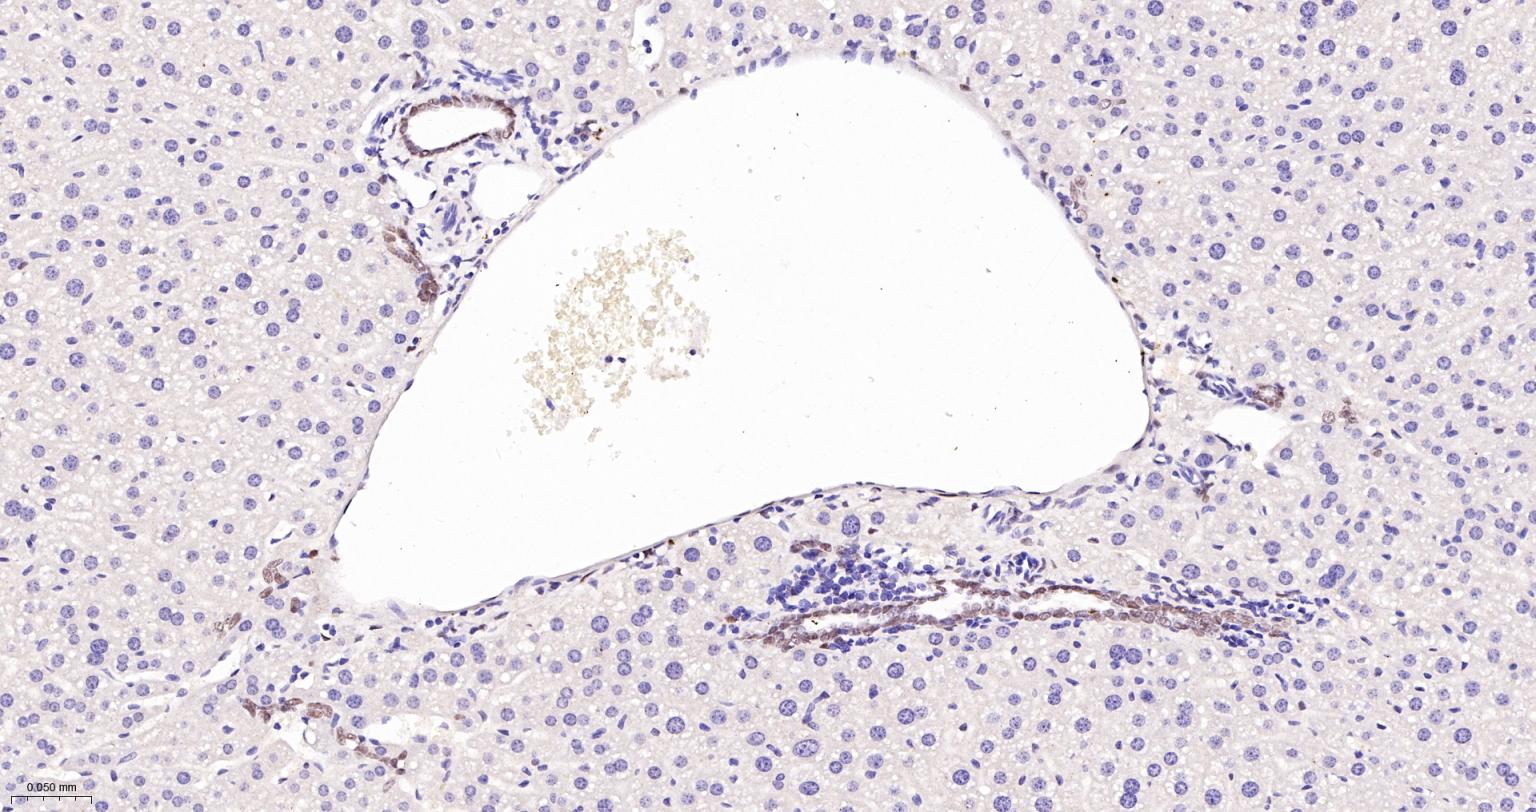

Paraformaldehyde-fixed, paraffin embedded Rat Liver; Antigen retrieval by boiling in sodium citrate buffer (pH6.0) for 15 min; The section was incubated with TEAD1 Monoclonal Antibody, Unconjugated (bsm-63274R) at 1:200 overnight at 4°C, followed by conjugation to the bs-0295G-HRP and DAB (C-0010) staining.